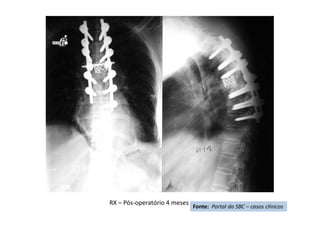

• Cifose pós-traumática

• Resumo do caso: Queda da própria altura com diminuição de força de

membros inferiores de forma gradativa.

• Paciente (dados): Sexo feminino, 54 anos

• História: Queda da própria altura durante internação hospitalar em outro

serviço para tratamento de crise de ativação do LES há 6 meses. Apresentou

diminuição de força de membros inferiores de forma gradativa. Foi avaliada

no serviço de origem e realizado TC e aventada a hipótese de mielite

transversa. Foi encaminhada ao CRER para reabilitação. Nesse momento

apresentava apenas parestesia em MMII e FM grau 0 (ASIA B).

• Diagnóstico(s): Consolidação viciosa de T5, com cifose pós-traumática e

compressão medular (ASIA B)

• Antecedentes de Lúpus (LES), uso crônico de corticóide e tabagismo severo

• Tratamento(s): Realizada vertebrectomia com descompressão medular e

reconstrução com Mesh CAGE e artrodese de T2 a T8 por via posterior.

• Seguimento ("Follow up"): PO 1 ano com boa melhora funcional da

paciente.

• Resultado Final: Paciente apresentou melhora gradativa da força muscular e

da função, estando hoje com força muscular grau IV em MMII, conseguindo

deambular e inclusive subir e descer escadas com apoio (ASIA D).

Fonte: Portal da SBC – casos clínicos

RX – Pós-operatório 4 meses